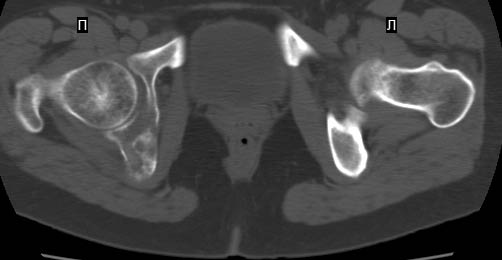

Сохранная по соматической патологии женщина ,47 лет. В 1996 г. установлен диагноз- cr левой молочной железы Т2N1Mo (2б)- проведено комплексное лечение- мастэктомия по Холстеду, ДГТ, 5 курсов ПХТ по схеме CMF. Сейчас менопауза уже 6-7 лет. В декабре 2004 года на профилактической остеосцинтиграфии с Тс99- выявлен единичный очаг повышенной фиксации препарата в зоне правой седалищной кости, рекомендована Рентгенография костей таза, выполнена- без патологии. УЗИ брюшной полости и Р-графия легких от конца апреля 2005 года - без патологии. Приблизительно 3 месяца назад появился болевой синдром в правом т/бедренном суставе с тенденцией к усилению. На рентгенограмме таза от мая 2005 года по заключению Рентгенолога очагов остеодеструкции не выявлено. Сегодня сделал ей Кт костей таза (картинки в приложении)- очаг деструкции в правой седалищной кости в зоне крыши вертлужной впадины.Что можно и нужно сделать? Жду советов, мнений, предложений по дальнейшей тактике ведения больной. С уважением, Корнев А.В.

Сам не имея опыта лечения подобных больных, сегодня показал представленные снимки специалисту по костной онкологии (Dr. Kurt Merkel), партнеру по работе.

Его мнение: в данный момент облучение не более 2000-3000 рад, через три недели операция по удалению процесса "кюретажным методом" затем ввести несколько спиц с резбой на конце в различных направлениях (создавая как бы внутренную арматуру) метод Harrington?, потом полость залить цементом, вариант костной пластики тоже не исключает.